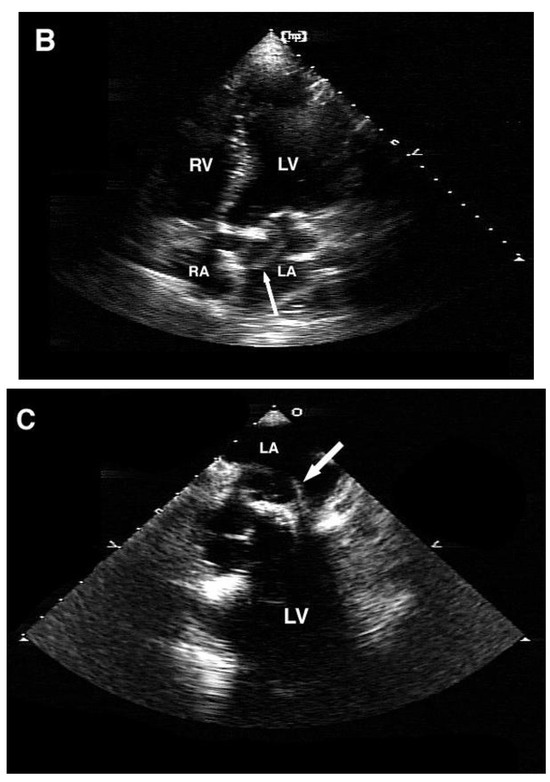

Carotid Restenosis: Incidence, Pathophysiology and Therapeutic Options

Restenosis after carotid endarterectomy and carotid artery stenting remains the main complication after both surgical and endovascular treatment of carotid stenosis, with a 2-year restenosis rate of 6–12%. Complex inflammation processes are the cause of early (<2 years) and late (>2 years) restenosis [...] Read more.

Restenosis after carotid endarterectomy and carotid artery stenting remains the main complication after both surgical and endovascular treatment of carotid stenosis, with a 2-year restenosis rate of 6–12%. Complex inflammation processes are the cause of early (<2 years) and late (>2 years) restenosis and principal systemic risk factors are female gender, hypertension, diabetes, dyslipidemia, and smoking. Non-procedural treatment includes lifestyle modifications and best medical therapy. The procedural treatment, considered mostly for symptomatic patients, includes different open and endovascular techniques. The management should be personalized according to patient and plaque characteristics. Full article

Graphical abstract